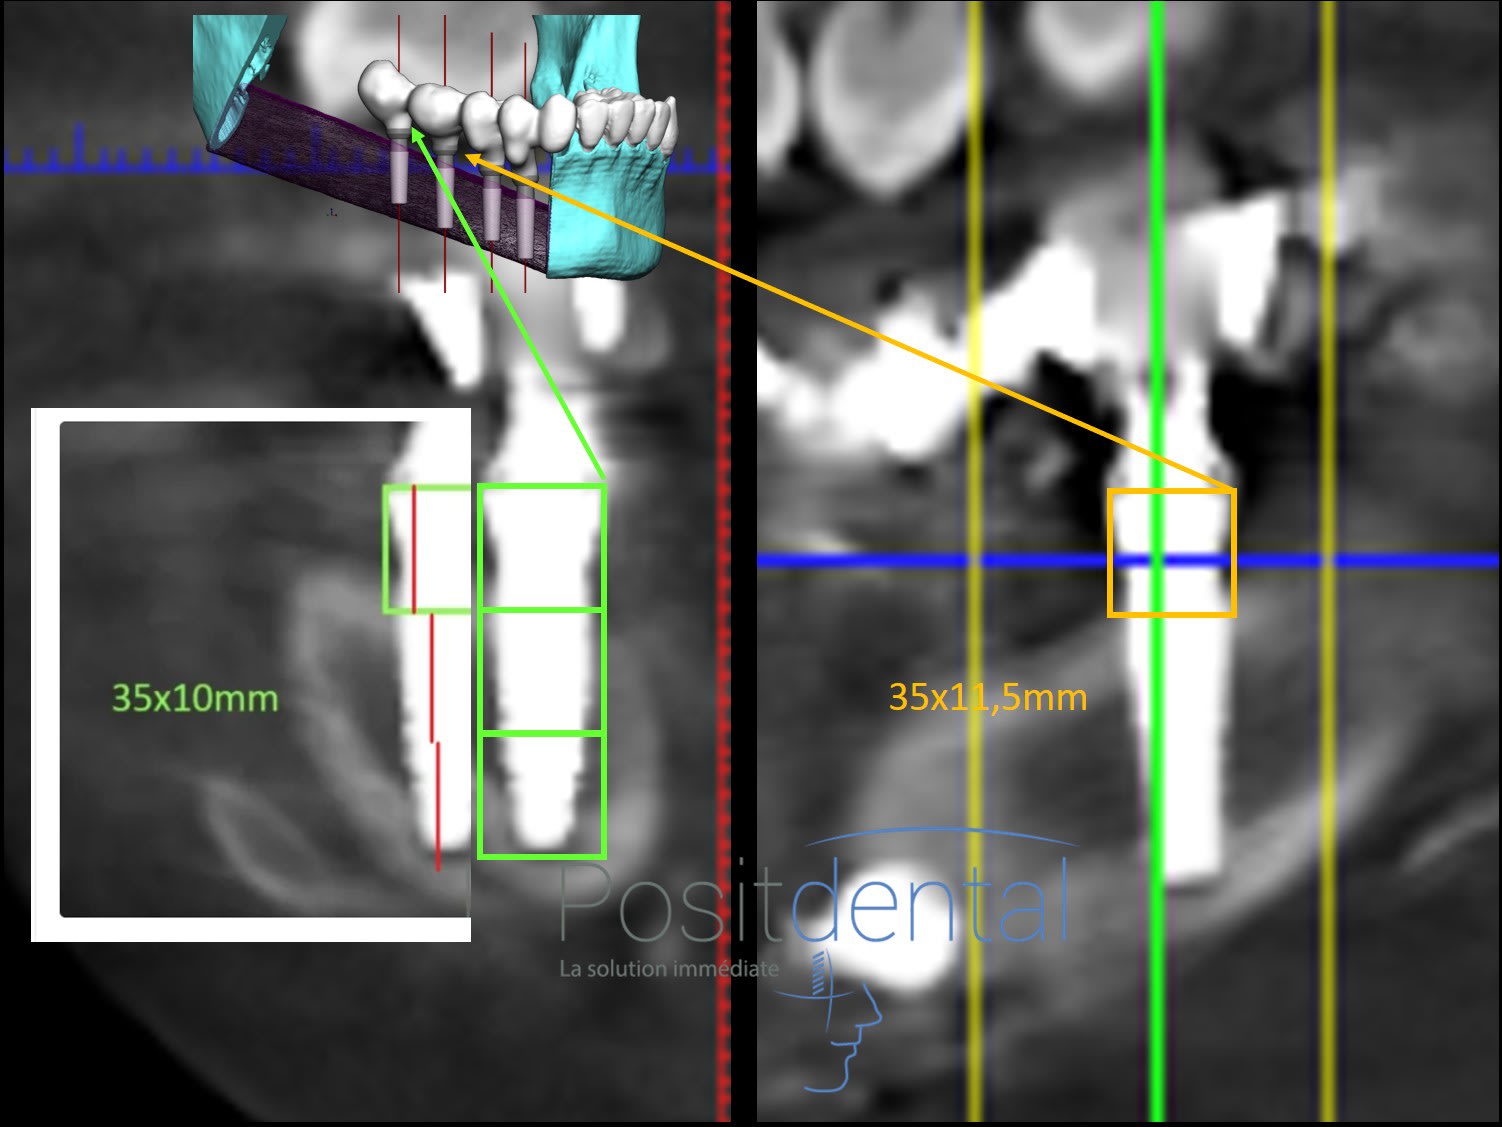

Pourquoi sur la coupe scaner ce trait ne forme pas un carré avec le MU?

Parce que tes histoires de carré n'ont aucun sens.

Regarde bien ta coupe, compare avec l'image de l'implant et tire les bonnes conclusions.

Tu vois le rétrécissement au niveau de la connection ? Je l'ai marqué avec des flèches rouges. Le col il est là et nulle part ailleurs

Ce qui n'a pas de sens et de refuser une methode qui donne une cote prècise pour controler le niveau du col de l implant

> une methode qui donne une cote prècise

lol... précise ?? si le trait rouge fait 4.5mm ton implant fait 7.8mm-8mm au max au lieu de 10mm.

c'est pas tres beau de piper autant son iconographie... surtout que ca trompe personne.

Fait des carré pour être précis